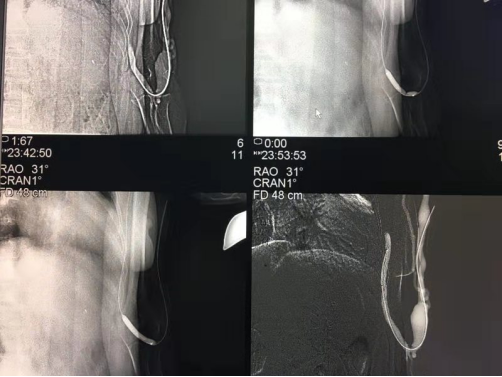

近日,我院放射科、介入室联合完成我市首例DSA下动静脉内瘘狭窄球囊扩张术。患者曾X某,女,69岁,诊断“尿毒症”,目前于我院血液透析中心长期接受血液透析治疗。近期,患者透析过程中反复出现透析困难,透析效果差等问题。血管超声检查发现,患者的左臂动静脉内瘘血管静脉狭窄,造成透析时内瘘血管血流量明显不足。我院肾内科及介入科联合会诊后,认为患者诊断明确,有行“DSA下动静脉内瘘狭窄球囊扩张术”治疗指征,无明显禁忌症,经与患者及家属沟通并取得同意后,于2019年8月21日在我院导管室行介入治疗。术后第二天,患者内瘘血管流量较术前明显增加,透析质量显著提高,取得了良好的疗效。